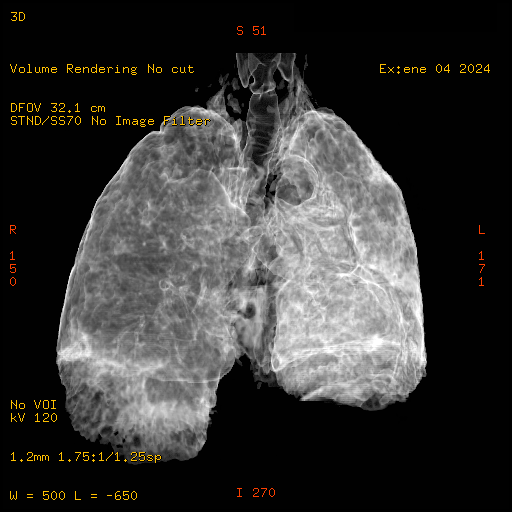

Se coloca al paciente en posición decúbito supino sobre la mesa de tomografía, se le solicita que suba los brazos hacia arriba de la cabeza, se le da las instrucciones para la respiración, se realizan cortes con grosor de 3.75 y un pitch de 1.7, realizando reconstrucciones retrospectivas en diferente plano, diferente grosor utilizando diferentes opciones de software que nos presenta el equipo.

El parénquima pulmonar izquierdo muestra un infiltrado intersticial difuso que causa engrosamiento del septum axial, además del fenómeno de bronquiectasias quísticas se observan pequeñas bulas enfisematosas de localización subpleural que compromete ambas bases pulmonares.

Al utilizar un contraste Minip, se observan bronquiectasias cilíndricas en el extremo del lóbulo superior derecho, observándose un patrón de panal de abeja situada en la región apical del lóbulo superior izquierdo.

Bronquiectasias cilíndricas, bullas enfisematosas basales bilaterales